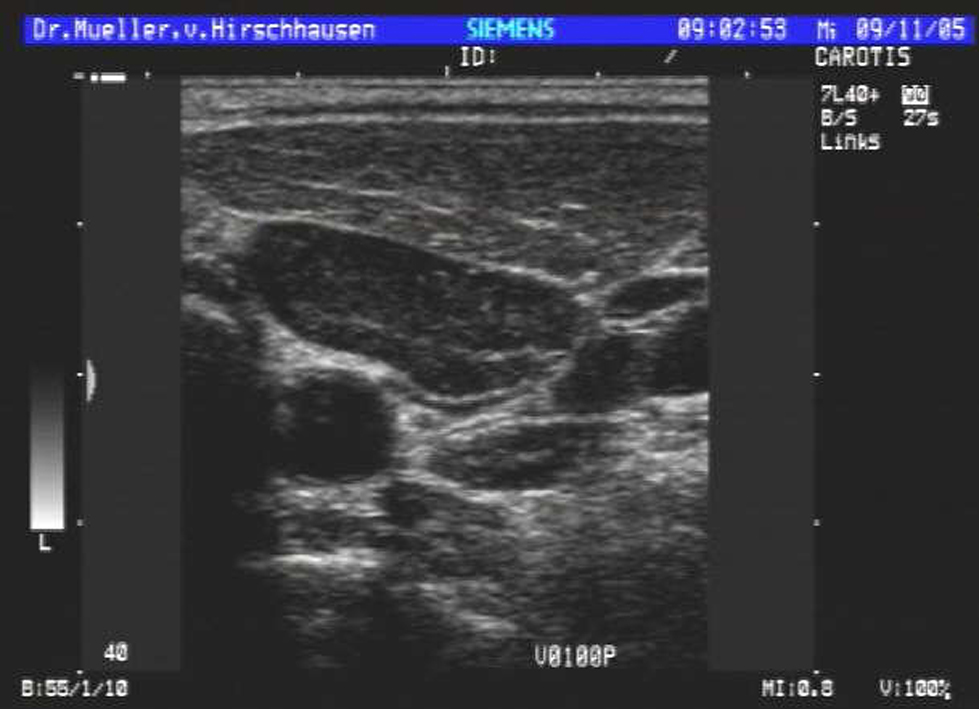

| Hals- und Gesichtsweichteile |

| Halsschlagader | |